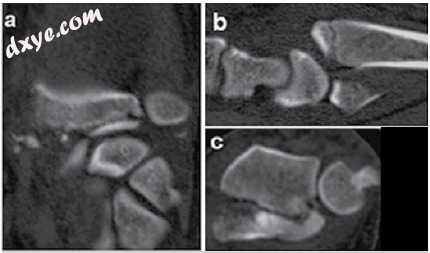

IIA  - 关节内远端放射性尺骨和/或桡腕关节内骨折,关节碎片间距≥2mm,无背角≥20°。 这些骨折没有表现出≥9mm的径向缩短。 (图4A-C)

4.jpg

图4

冠状面(A),矢状面(B)和轴面(C)平面上的断层图像描绘了桡骨远端的关节内桡腕和远端桡骨远端骨折,关节间距≥2mm,无角度和无 来自IIA组的径向高度损失≥9mm。